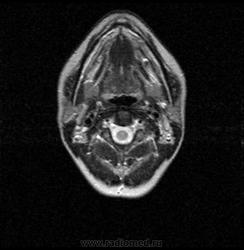

06.06.2011 МРТ - головы и шеи.

Пацентка 36 лет, с жалобами на припухлось в околоушной области справа.

В глубокой доле  правой околоушной железы  на фоне неизмененной паренхимы зона  гетерогенного по Т2, гипоинтенсивного по Т1  с единичными гиперинтенсивными включениями.При контрастировании- накопление контраста диффузное неоднородное и по периферии.Рискну предположить злокачественное образование ( аденокарцинома) с низкой степенью злокачественности( есть капсула, экспансивный рост).Сильно не расстреливайте.

Проблема в том, что перед челюстно-лицевым хирургом стоит распространенность любого объемного процесса, в данном случае все упирается в возмможную травму лицевого нерва и конечно же с дальнейшим его парезом, а ведь женщина  еще молодая. Образование имеет тонкостенную оболочку, по структуре неоднородно, с наличием кальцината, при этом МР-сигнал от окружающих анатомических структур(как костных так и мышечных) не изменен, т.е. об инфильтративном росте речи не идет, в какой то степени доброкачественное. В конкретном случае лицевой нерв с ретромандибулярной веной просто несколько оттеснен.

По гистологии аденома околоушной слюнной железы, но после удаления пока сохраняется парез лицевой мускулатуры, возможно временный.